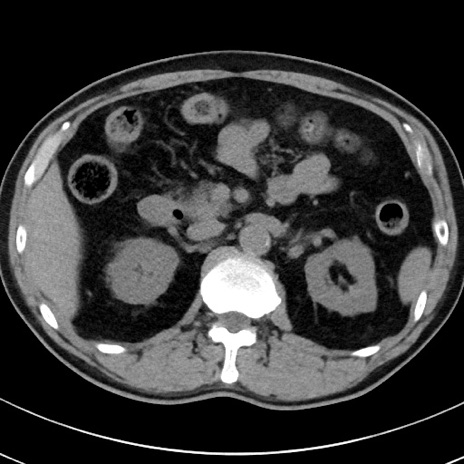

【腹部TIPS】症例29 参考症例 CT(横断像)

症例

70歳代男性